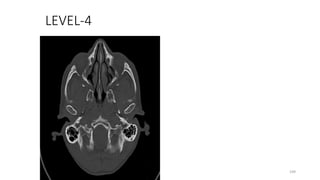

LEVEL-4

109

Basiocciput (posterior clivus)

110

Hypoglossal canal

111

Pterygopalatine fossa

112

Pterygoid plates

113

Pterygoid process

114

Occipitomastoid suture

115

Occipital bone (squamous part)

116

Pterygomaxillary fissure

117

Sphenoid, greater wing

118

Sphenoid spine

119

Sphenopalatine foramen

120

Styloid process, base

121

Zygomatic arch

122

Zygomaticofacial foramen / canal